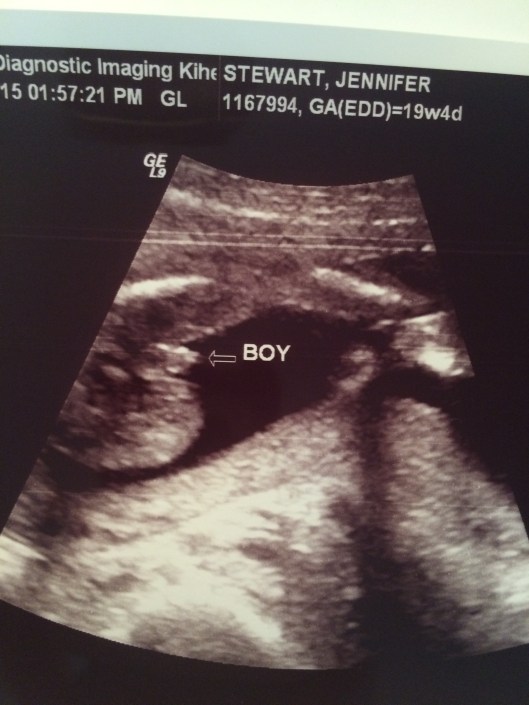

As I sit here staring at my beautiful son I am extremely aware of how quickly time passes. If I listen close enough I would swear that I could literally hear the seconds ticking away. As I listen, my skin covered in goose bumps I still can’t pull away from sitting and staring. It’s hard to believe 7 weeks ago I was preparing myself to meet him. So many thoughts and feelings and questions. What would he look like? How would he be? Would he be healthy? Would he know I was his mom?